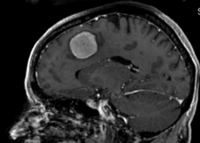

Intra-subject Brain MRI: axial T1 Tumor Growth Assessment

this is the fixed reference image. All images are aligned into this space lleft this is the moving image. The transform is calculated by matching this to the reference image

fixed image/target moving image

This is a typical case of change assessment. We want to know if/how the tumor changed since last exam.

MRI, brain, head, intra-subject, T1, tumor growth, meningioma, change assessment

• reference/fixed : T1 SPGR , 0.9375 x 0.9375 x 1.4 mm voxel size, axial, RAS orientation.

• moving: T1 SPGR , 0.9375 x 0.9375 x 1.2 mm voxel size, sagittal, RAS orientation.